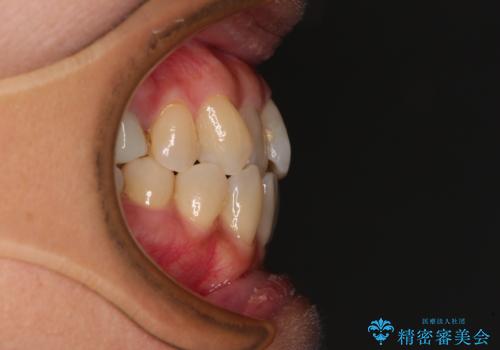

受け口と八重歯を改善 インビザライン矯正治療

- 前歯のデコボコや八重歯を治したいとのことで来院された患者様です。

受け口傾向の骨格であり、前歯はクロスバイトまたは切端咬合となっており、下顎を中心に歯列全体の後方移動を行い、IPR(歯と歯の間を削る)によってデコボコが解消するように設計し、インビザラインにより治療を行うこととしました。

受け口傾向のインビザライン矯正は比較的治療を行いやすいため、きれいに仕上げることができました。舌の突出癖が顕著であったため、改善のためのトレーニングをしっかりと行っていただきました。